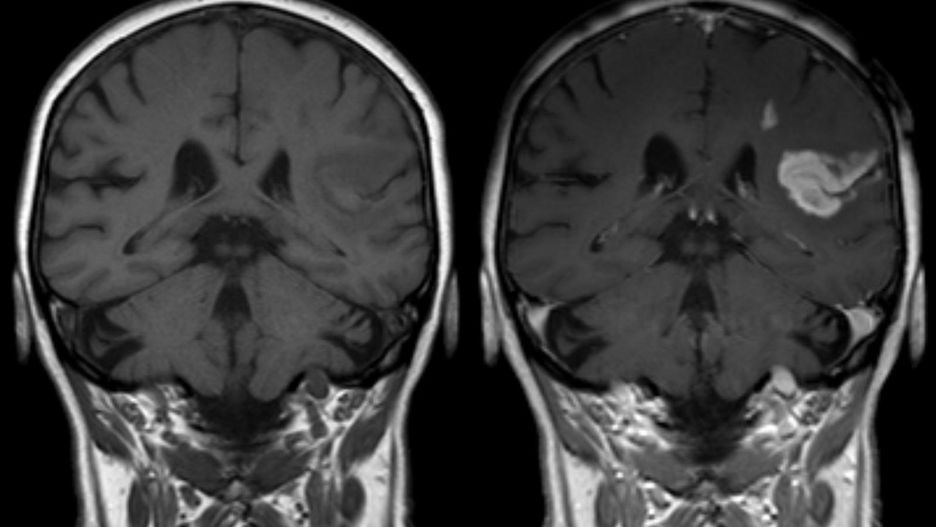

Kluczowy jest rezonans magnetyczny (MRI). To na jego podstawie brytyjscy specjaliści pokusili się o ustalenie prawdopodobieństwa śmierci.

Sprawdzili tysiące skanów mózgu zdrowych ludzi. Specjaliści z Imperial College w Londynie użyli bardzo wielu wyników rezonansu magnetycznego do sporządzenia wzorca, który pozwala im ocenić wiek tego organu - informuje Sky News. Doktor James Cole udoskonalił metodę opracowaną w 2010 roku, dzięki której można zmierzyć urządzeniem MRI objętość mózgu i oszacować, stopień utraty istoty szarej i białej.

Wzorzec mózgu przyłożyli do konkretnych osób. Specjaliści sięgnęli po wyniki grupy 669 osób, które uczestniczyły w długoterminowym badaniu zdrowotnym Lothian Birth Cohort 1936 (ludzie urodzeni w 1936 roku). Przeszli oni prześwietlenie MRI w 1973 roku. Właśnie z użyciem tych wyników i swojego wzorca Brytyjczycy z londyńskiej uczelni doszli do swoich wniosków.